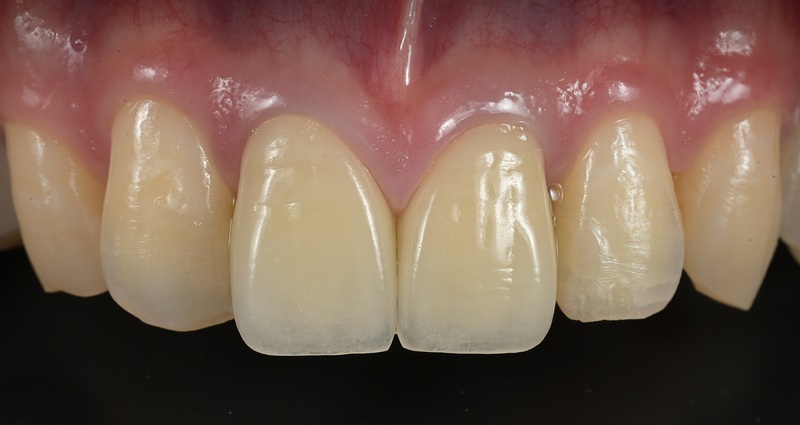

術後

以前に治療された前歯の被せ物の見た目を気にされ、再治療をご希望されました。 審美性だけでなく、内部の根管治療まで丁寧に行うことで、将来的なトラブルのリスクを抑えた、長期的に安定した治療結果を目指しました。 |